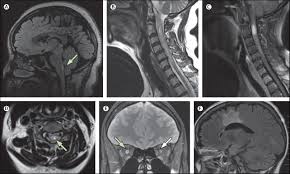

今回、上記3種類の遺伝子ワクチン接種後の代表的な脱髄疾患(多発性硬化症(MS: multiple sclerosis)、横断性脊髄炎(TM: transverse myelitis)、急性散在性[播種性]脳脊髄炎(acute disseminated encephalomyelitis (ADEM))、視神経脊髄炎スペクトラム障害(neuromyelitis optica spectrum disorder (NMOSD))、抗MOG(抗ミエリンオリゴデンドロサイト糖蛋白質)抗体関連疾患(myelin oligodendrocyte glycoprotein antibody disease (MOGAD)))の発症例を調べた研究が報告されています(A systematic review of cases of CNS demyelination following COVID-19 vaccination. J Neuroimmunol. 2022 Jan 15; 362: 577765)。